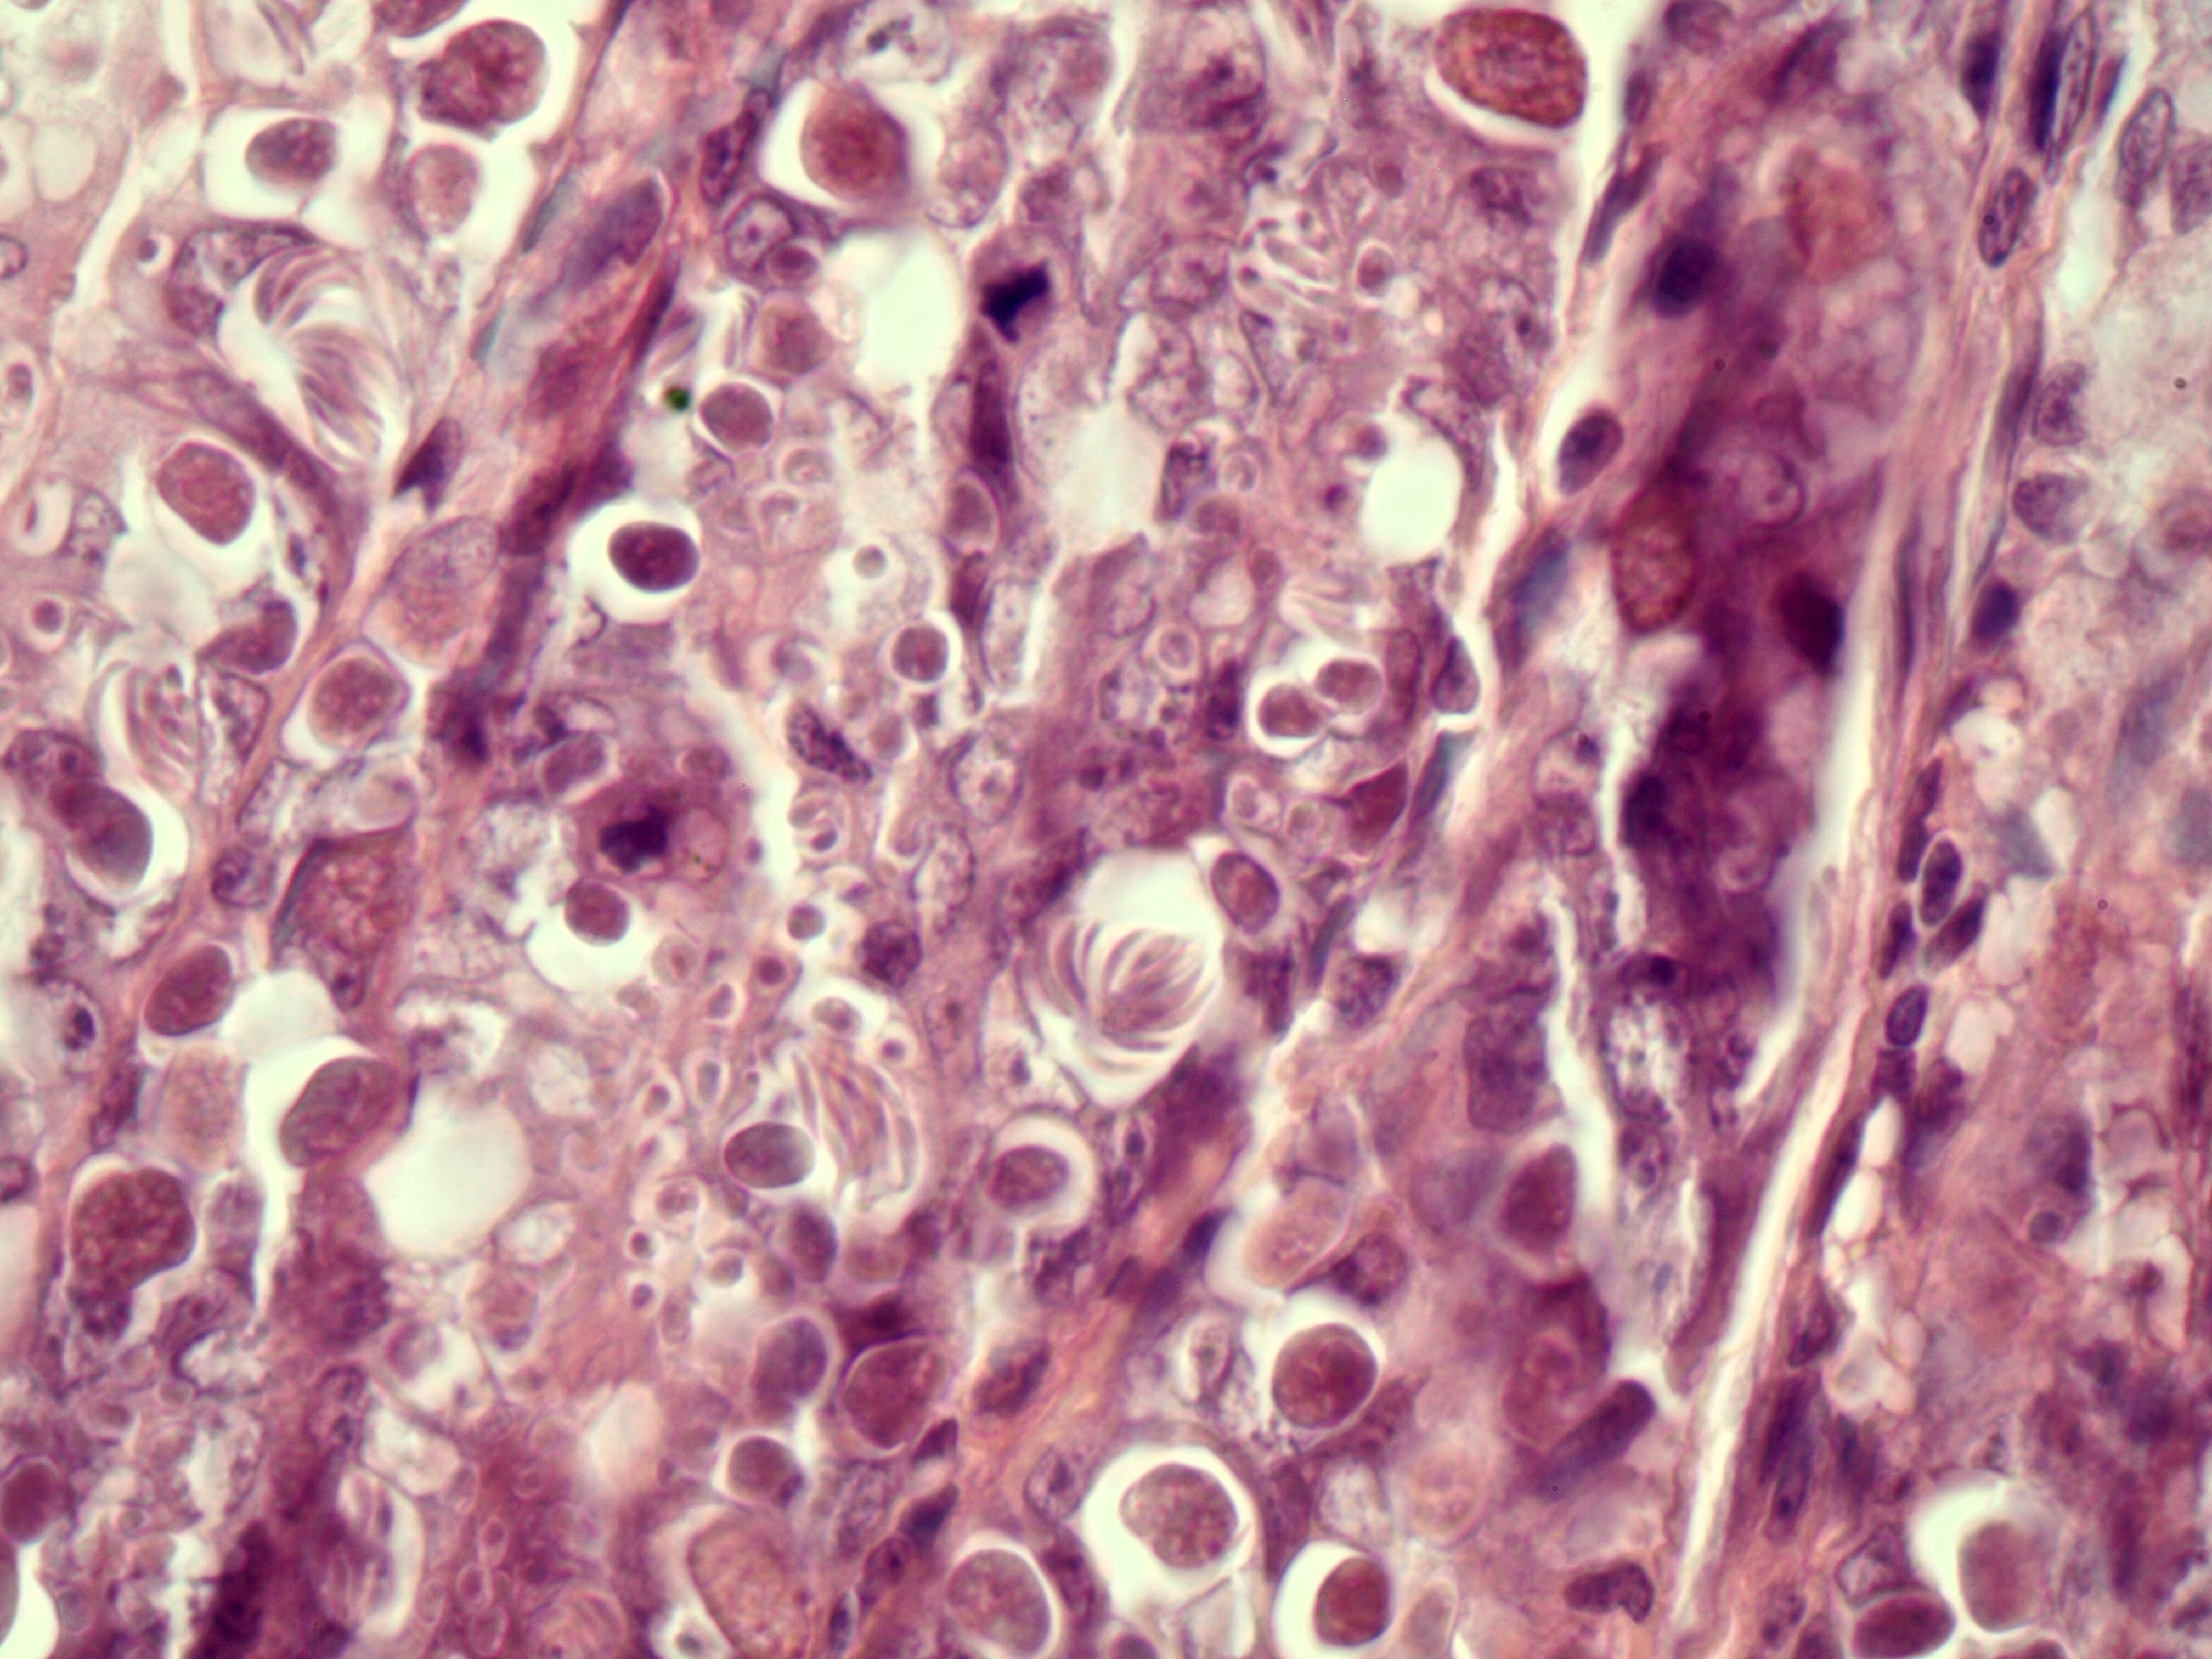

"Estos parásitos se reproducen en las células epiteliales del intestino delgado. Al reproducirse, rompen las células, el roedor enferma y hasta muere. Decidimos estudiar el ciclo de vida para ver cómo el animalito se infecta y cómo es el proceso de la enfermedad", añadió.

En este momento, de acuerdo con el investigador, el parásito toma una forma de "amebita" que se reproduce dentro de la célula. Esta fase activa recibe el nombre de tropozoito.

Posteriormente, se transforma en tres tipos de estructuras llamadas esquizontes (palabra derivada de "esquizo" que significa "división" en griego).

Los esquizontes son "células madre" que dan origen a hijas llamadas merozoitos. Cada uno de los merozoitos inicia un ciclo sexual con partes femeninas y masculinas que se unen y forman un cigoto.

Esta forma de cigoto recibe el nombre de ooquiste y toma todo el ADN y ARN de la célula del roedor que invadió. La membrana celular se destruye y el oquiste sale hacia otra célula para iniciar de nuevo un ciclo de vida.

"Cada ooquiste tiene ocho esporozoites y cada uno penetra en una célula diferente. Debemos tomar en cuenta que en cada infección puede haber unos 50.000 ooquistes en este proceso, y por eso, en ocasiones, resulta letal", subrayó Chinchilla.